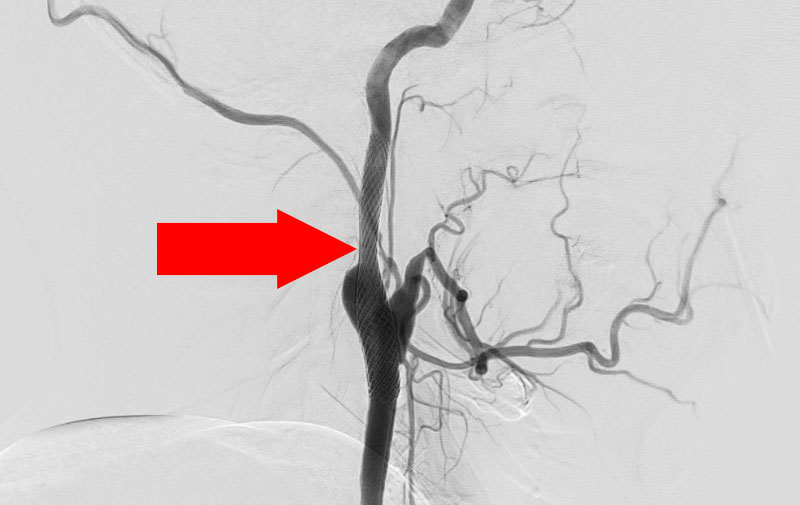

No.1210 手術中

右頚部内頚動脈狭窄症

80代

大阪府の病院